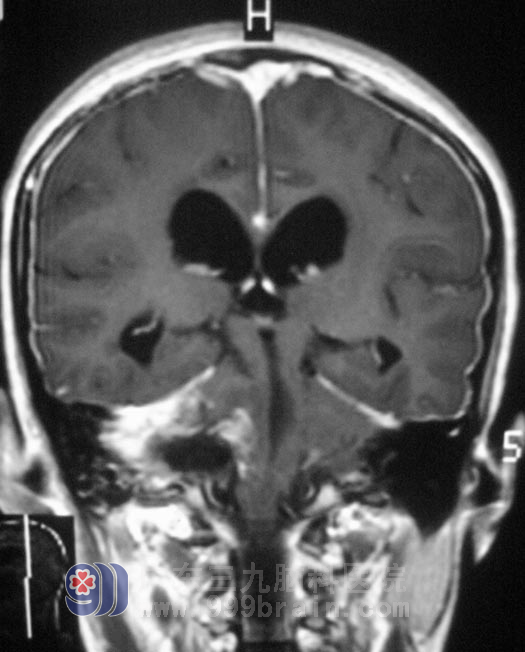

二十岁的小何,两个月前因右耳听力下降伴头痛、头晕,检查发现右侧桥小脑角区囊实性占位,直径约4.5cm,伴幕上梗阻性脑积水,在当地医院行右侧桥小脑角区肿瘤切除手术,术后肿瘤残留。小何一直存在右耳听力障碍,头痛、头晕症状逐渐加重。二周前她开始出现间断呕吐,走路不稳,双眼视力下降。这是一次不是很满意的手术治疗。

2月23日,由综合神经外科 鲁明主任主刀,在全麻下行右侧桥小脑角区残留肿瘤切除术,术中取原切开入路,显微镜下见肿瘤位于右侧桥小脑角,呈黄白色,周围纤维组织增生明显。显微镜下分块切除,术中电生理检测,右侧听神经形态菲薄,面神经位于肿瘤前下方,舌咽神经、迷走神经位于肿瘤后下方,与肿瘤粘连紧密,细心分离完整保留,残留肿瘤全切,手术顺利结束。术后经过治疗,小何未出现吞咽困难、构音障碍、面瘫等症状,可以自行行走,已满意出院。术后病理结果:神经鞘瘤。